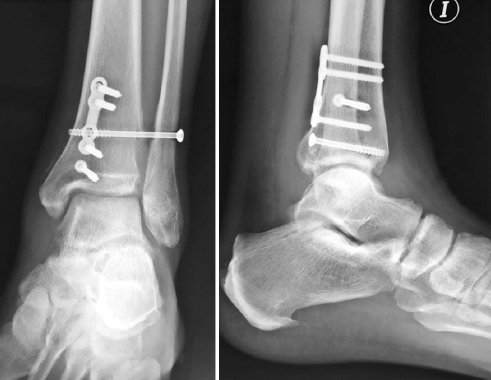

Se procedió con la resección artroscópica de los fragmentos condrales y reducción guiada por artroscopía de la sindesmosis, la cual se mantuvo con un tornillo transindesmal canulado de 4.0 × 55 mm. A través de un abordaje medial se realizó la osteosíntesis del maléolo posteromedial con un tornillo canulado de 4.0 × 36 mm y placa A.L.P.S.® foot straight fusion de 3.5 mm (Zimmer Biomet) (Fig. 4). Utilizando el mismo abordaje se realizaron dos microperforaciones a nivel de la lesión condral del astrágalo y se reparó el ligamento deltoideo con un ancla BioComposite SutureTak® Mini (Arthrex) de 2.5 mm. Se decidió tratar la ruptura del ligamento peroneoastragalino anterior de manera conservadora.

Figura 4. Imágenes transoperatorias. Se observa el trazo de fractura posteromedial durante la cirugía en dos planos sagitales y se compara con la imagen radiológica.